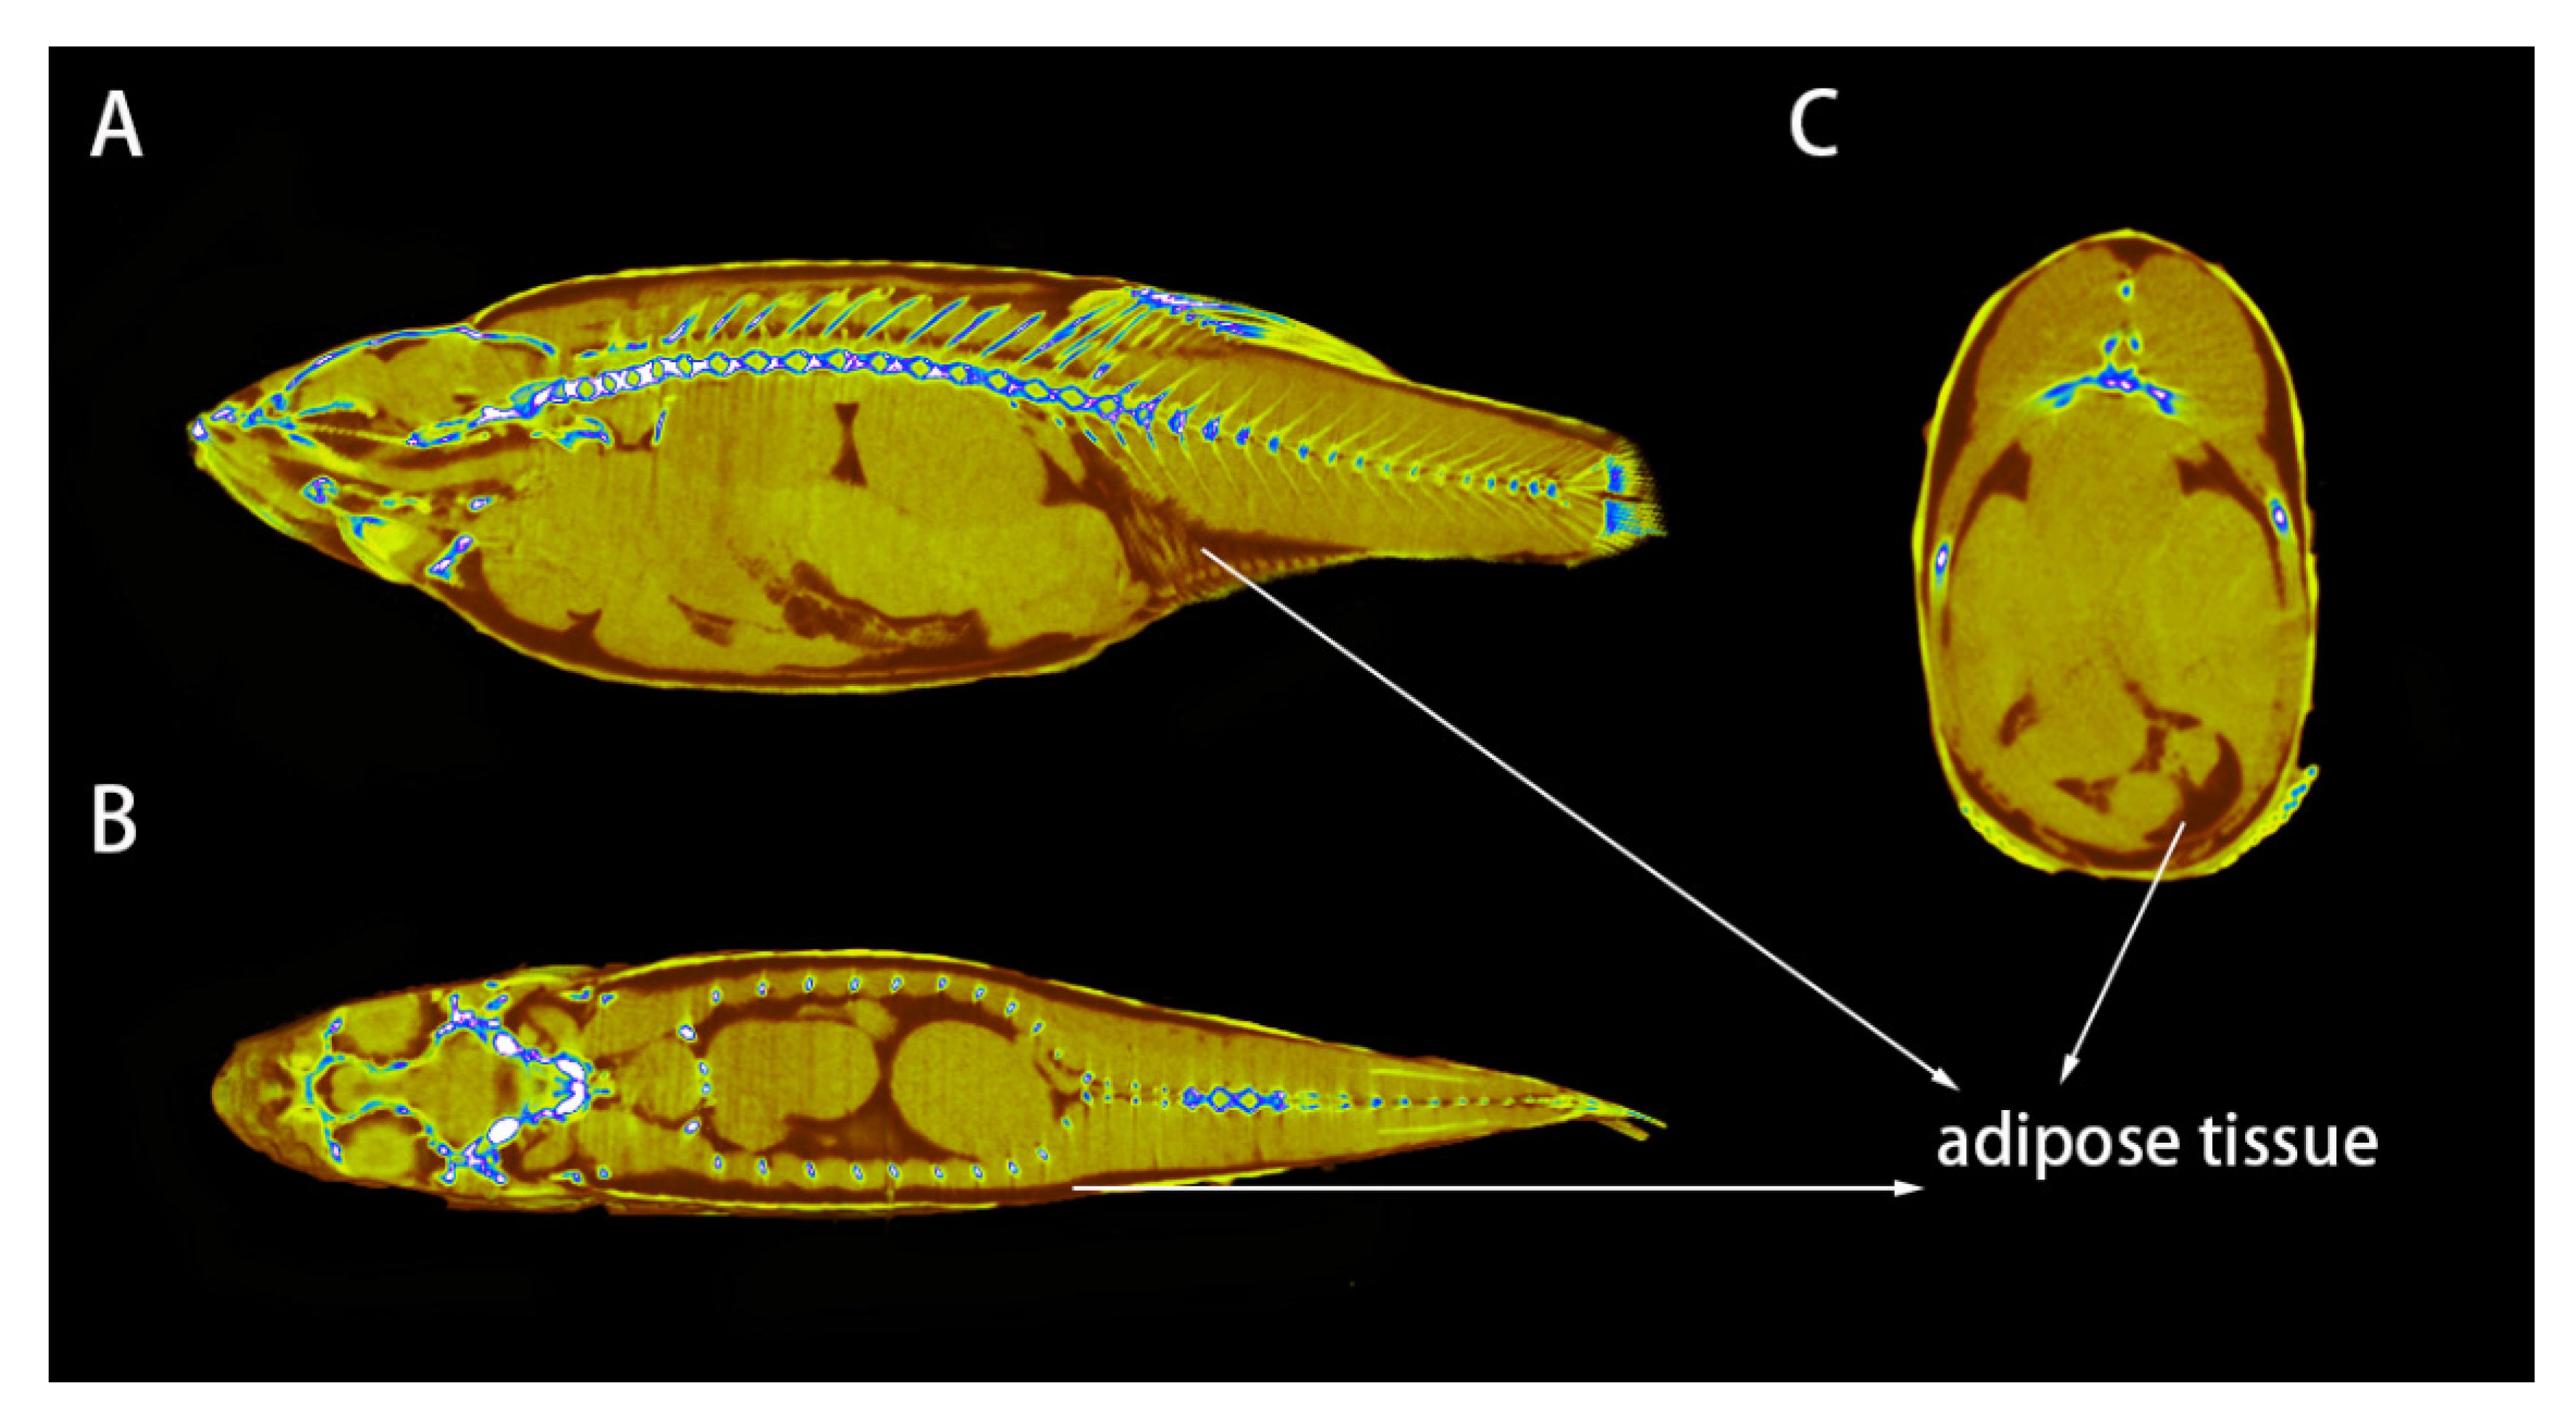

3.2. Distribution of Adipose Tissue in Zebrafish

3.1. Method to Detect Adipose Tissue in Zebrafish by CT Scanning

2.6. Construction of the 3D Model of Adipose Tissue